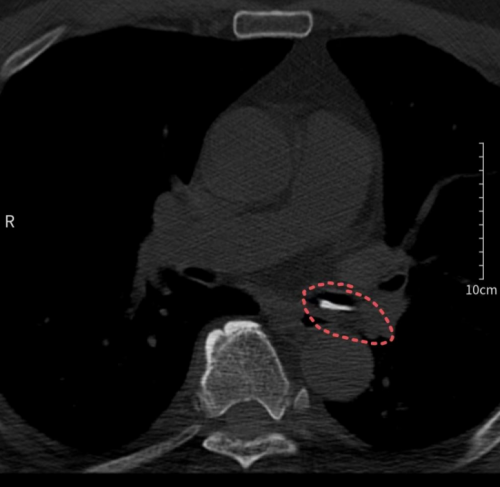

进入立博体育 后,刘建军接受了胸部CT检查。接诊的耳鼻咽喉头颈外科副主任、副主任医师周定刚及主治医师文杰,在详细询问刘建军的经历并仔细阅读CT影像片后,发现其左侧支气管处有高密度影,但食管未见明显破损。他们迅速判断为支气管异物,并立即联系呼吸与危重症医学科进行紧急会诊。

胸部CT检查发现异物在左侧支气管为确保患者安全,医生们决定立刻为刘建军实施纤支镜下异物取出术。呼吸内镜诊疗中心副主任医师刘超群从家中赶来,迅速为刘建军进行了纤支镜检查及支气管异物取出术。术中,医生成功从患者支气管内取出两块正方形的甲鱼背壳骨片。从患者入院到异物取出,整个过程仅用时1小时,确保了患者的安全。